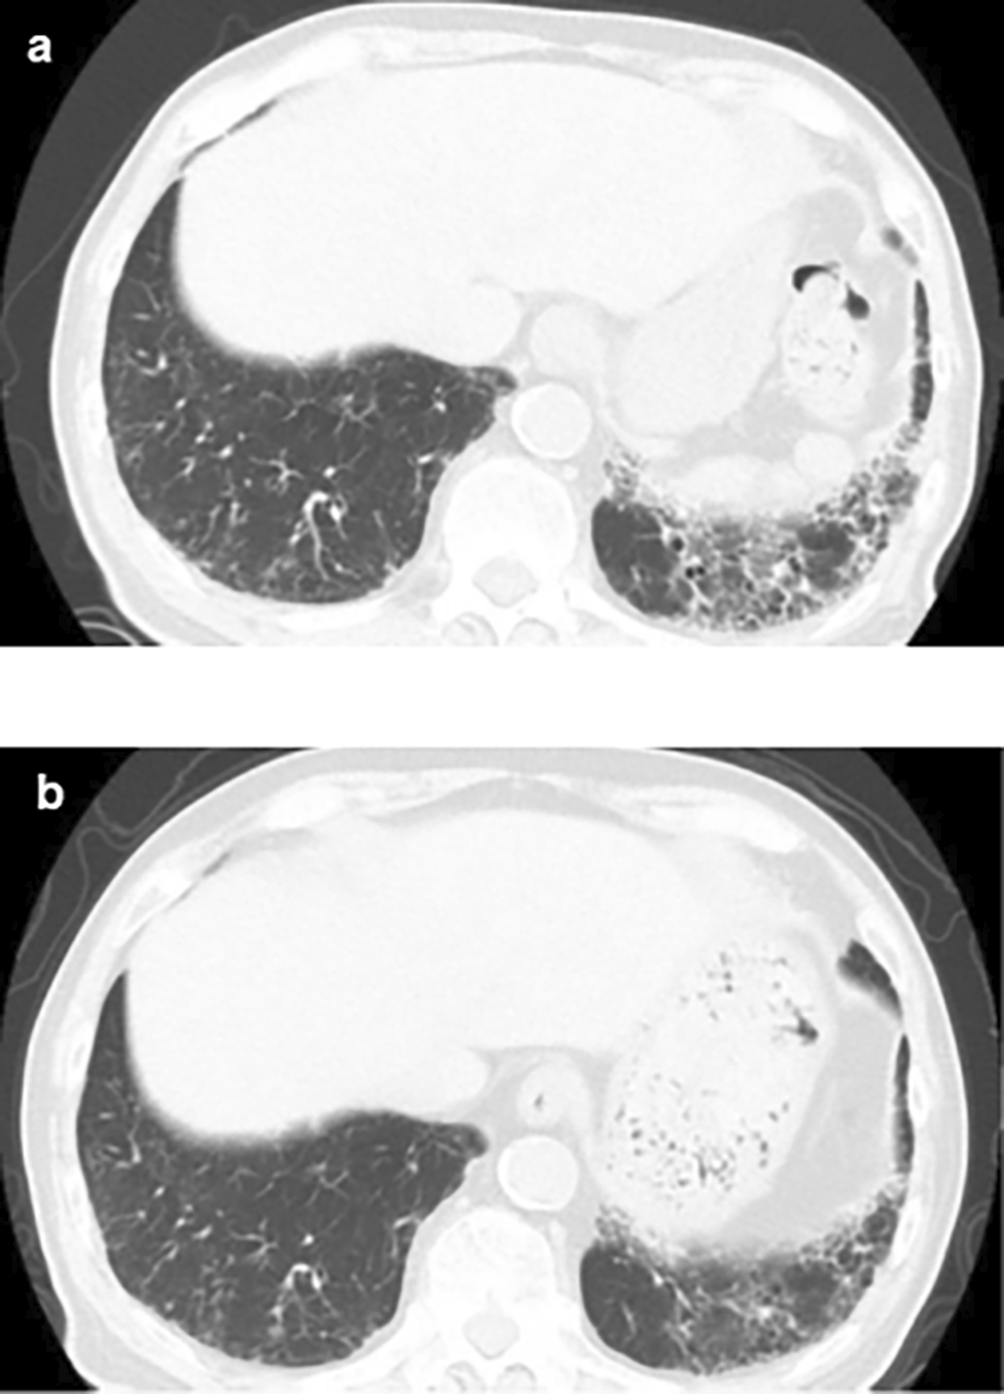

An 84-year-old unemployed Japanese man presenting with dyspnea on exertion and cough was referred to our hospital. The patient had a history of hypertension and hypothyroidism, but an unremarkable family history of any related pathology. Examination results of the patient were found to be negative for arthralgia, skin rash, macrohematuria, and hemoptysis. Upon admission, body temperature was recorded to be 36.5 °C; blood pressure, 128/72 mmHg; heart rate, 72 bpm; oxygen saturation, 98%; weight, 60.5 kg; height, 164.9 cm; and BMI, 21.1 kg/m2. Initial laboratory and diagnostic workup revealed blood urea nitrogen 18 mg/dL (normal range: 8-20 mg/dL), creatinine 0.98 mg/dL (normal range: 0.65-1.07 mg/dL), estimated glomerular filtration rate 56 mL/min/1.73 m2 (normal range: ≥ 60 mL/min/1.73 m2), calcium 9.4 mg/dL (normal range: 8.8-10.4 mg/dL), total protein 9.1 g/dL (normal range: 6.5-8.0 g/dL), albumin 3.6 g/dL (normal range: 3.9-4.9 g/dL), alkaline phosphatase 60 IU/L (normal range: 50-350 IU/L), aspartate transaminase 27 IU/L (normal range: 7-38 IU/L), alanine transaminase 11 IU/L (normal range: 4-44 IU/L), total cholesterol 182 mg/dL (normal range: 120-220 mg/dL), triglyceride 175 mg/dL (normal range: 50-149 mg/dL), WBC 11.5×103/μL (normal range: 3.1-8.4×103/μL), RBC 3.97×106/μL (normal range: 4.2-5.7×106/μL), hemoglobin 12.5 g/dL (normal range: 14-18 g/dL), platelets 200×103/μL (normal range: 150-330×103/μL), eosinophils 3% (normal range: 0-5%), and urinalysis negative for protein, RBC, and cell casts. Urinary N-acetyl-beta-D-glucosaminidase (NAG)/creatinine 17.1 IU/gCr (normal range: 1.6-5.8 IU/gCr) and urinary β2 microglobulin 371 mg/L (normal range: ≤289 mg/L). Antineutrophil cytoplasmic antibodies screening was found to be negative, with low C3=68 mg/dL, low C4=7.4 mg/dL, and negative for anti-SSA, anti-SSB, anti-RNP, Scl-70, anti-Sm, and ds-DNA antibodies. Antinuclear antibodies (ANA) antibodies were found to be ×1280. Hyperglobulinemia was determined with an IgG level of 3719 mg/dL (normal range: 870-1700 mg/dL) and an IgG4 level of 1290 mg/dL (normal range: 4-108 mg/dL). Rheumatoid factor (≤15 IU/mL) was elevated at 24 IU/mL, and KL-6 (<500 IU/mL) was significantly increased at 623 IU/mL. Computerized tomography (CT) revealed bilateral ground-glass and reticular opacities predominantly in the lower and peripheral portions of the lungs (Figure 1a). Furthermore, bronchial wall thickening, and enlarged cervical, mediastinal, and axillary lymph nodes were identified. However, renal, pancreatic, or salivary gland inflammation was not observed. Ga-67 scintigraphy revealed accumulation in the kidneys (Figure 2). Consequently, the patient was diagnosed with IgG4-related kidney disease based on the renal pathology with massive tubulointerstitial nephritis, characteristic fibrosis (bird’s eye pattern) (Figure 3a and b), and IgG4-positive cell infiltration, wherein the number of IgG4 positive plasma cells was >10/hpf, and IgG4/IgG ratio was 61.9% (Figure 3c). Deposition of globulin or complement, and evidence of glomerular sclerosis were not observed in the glomeruli. Treatment was initiated by administering oral prednisolone at 30 mg/day for one month, followed by prompt alleviation of cough and dyspnea on exertion. With a subsequent decrease (after one month prednisolone treatment) in urinary NAG and β2 microglobulin and IgG4 levels, prednisolone was decreased from 2.5 to 5 mg every 2 to 4 weeks for 4 weeks. One year after the initiation of treatment, the patient achieved normalization of serum IgG4 levels, and chest CT revealed the interstitial pattern was found to have nearly disappeared (Figure 1b). Figure 4 shows the clinical course of this patient.

(a) Plain chest CT showing the reticular pattern and bronchial dilatation in the bilateral lower lung fields before therapy; (b) After therapy, the interstitial pattern nearly disappeared from the bilateral lung fields. CT: computed tomography.

CT imaging findings of the lungs in IgG4-related diseases have been classified into four types: ground-glass opacity, diffuse reticular, bronchial wall thickening, and nodular patterns.14 The ground-glass opacity and diffuse reticular patterns potentially suggest lymphocyte and plasma cell infiltration of the alveoli and interstitium. Bronchial wall thickening pattern indicates plasma cells infiltration of the bronchial vascular bundles, alveoli, and interstitium. Finally, nodular sclerosing inflammation of the bronchial glands was prominently observed to be associated with the nodular pattern.14 Although we did not perform a lung biopsy in the present case, the CT findings of diffuse reticular and bronchial wall thickening confirmed pulmonary involvement in IgG4-related diseases.